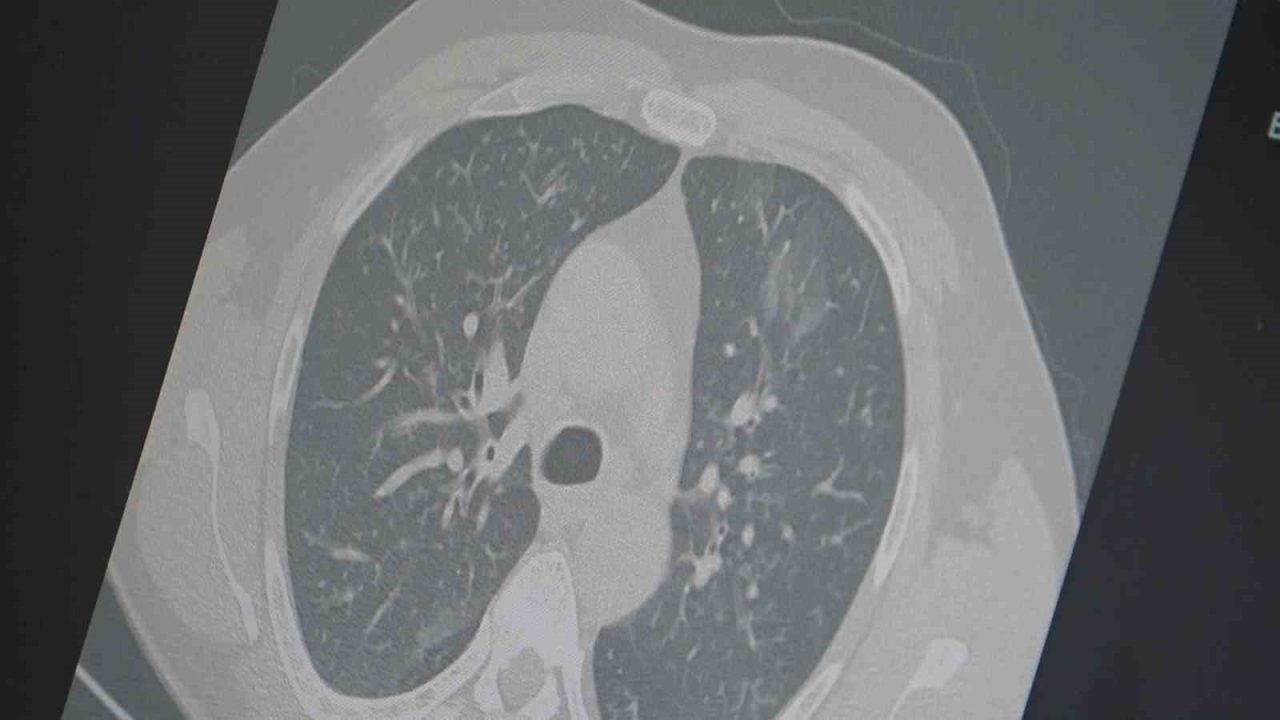

Dr. Özkaya, grip ve kovid 19’un zatürreye dönüşme riski taşıdığını vurgulayarak, “Grip veya kovid sonrası birçok hastamızda hastalık akciğerlere iniyor ve zatürre olarak karşımıza çıkıyor. Hastaneye yatan hasta sayısında da artış gözlemliyoruz” şeklinde konuştu.

“En ufak grip benzeri şikayeti olan vatandaşlarımızın evlerinde dinlenmelerini öneriyoruz. Uzamış öksürük ve nefes darlığı yaşayanların ise mutlaka doktora başvurarak akciğer röntgeni çektirmeleri ve uygun tedaviyi almaları gerekiyor.”